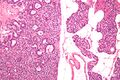

صورة مجهرية لغدوم الجار درقية (يسار) وغدة جارات درقية طبيعية (يمين). صبغة الهيماتوكسيلين واليوزين.

يتم تأكيد فرط نشاط جارات الدرقية عن طريق اختبارات الدم مثل مستويات الكالسيوم وهرمون الغدة الدرقية. اختبار محدد لغدوم الجار درقية هو التصوير الومضاني لغدة الجار درقية سيستاميبي. تكشف تقنية التصوير النووي هذه عن وجود وموقع أنسجة جارات الدرقية المرضية.[7]